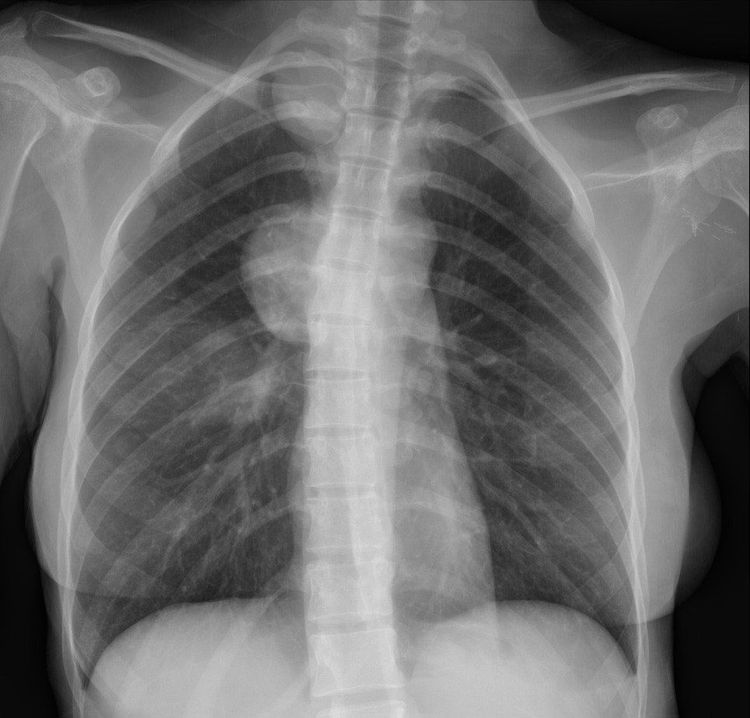

Chẩn đoán hình ảnh của hội chứng trung thất trên phim X quang bao gồm các dấu hiệu diễn tả sự hiện diện bất thường của các tế bào hoặc bệnh lý lạ xuất hiện tại trung thất, bao gồm: khí, dịch, u bướu hoặc đóng vôi.

2. Đặc điểm Xquang hội chứng trung thất

Xác định tổn thương thuộc trung thất trên phim X quang bằng các đặc điểm cơ bản sau:

- Bờ ngoài rõ, liên tục, bờ trong không rõ.

- Tạo góc tù với trung thất.

- Không có hình ảnh khí phế quản đồ.

Các dấu hiệu hình ảnh trong chẩn đoán hình ảnh xác định tổn thương trung thất: